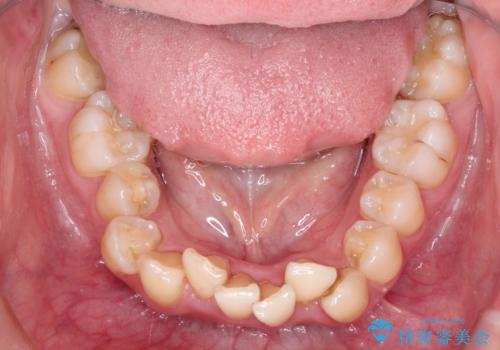

ガタガタの抜歯矯正を裏側ワイヤーを使っての目立たない矯正

- 八重歯とガタガタを主訴に来院されました。

目立たないワイヤー矯正を希望されたので、上下左右のはを1本ずつ抜歯して、ハーフリンガル(上顎だけ裏側)にて矯正をすることにしました。